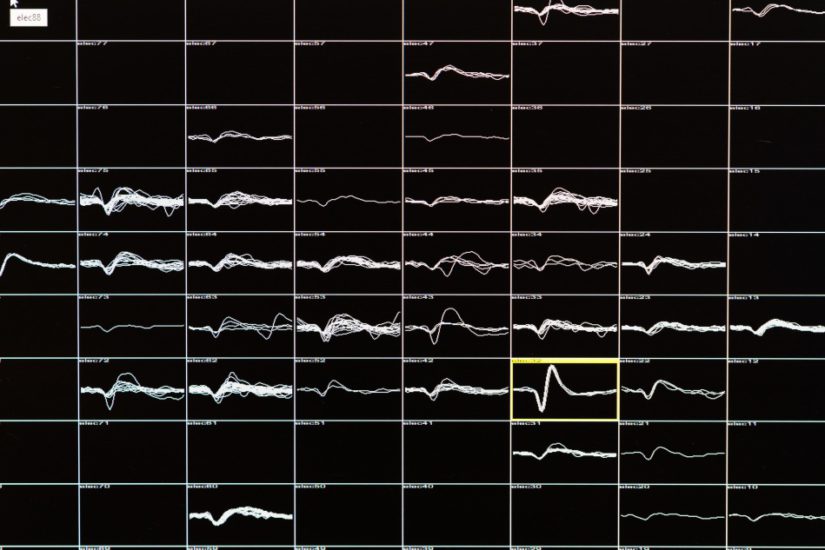

Impianti është i pajisur me 100 mikroelktroda të holla me gjatësi 1.5 milimetra të cilat nxisin qelizat nervore të kësaj zone.